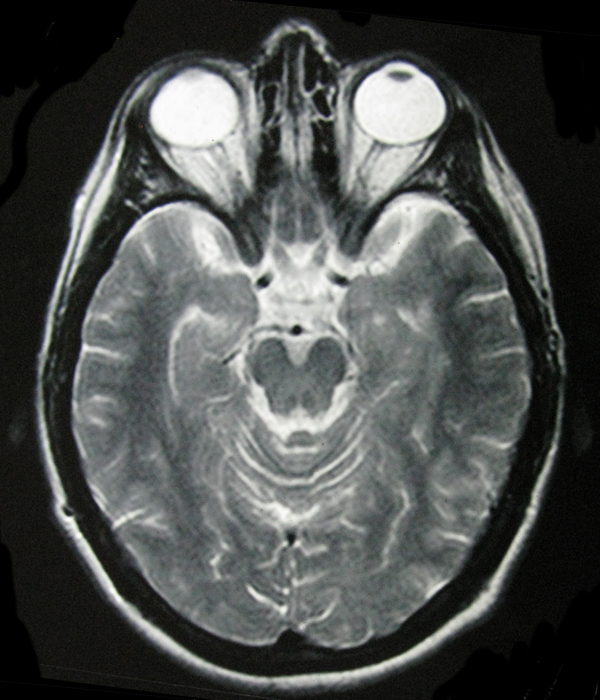

- My Brain in 2009